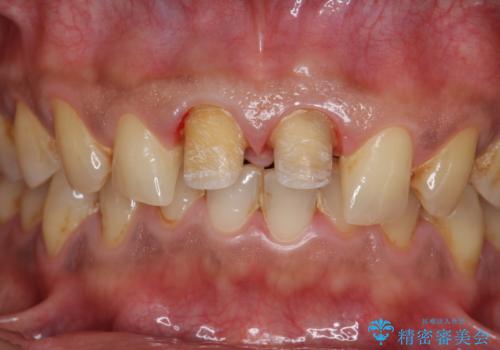

歯ぐきからの出血 膿が出る 前歯根管・セラミック治療

- 体調により前歯部の歯ぐきから出血や膿が出ることの改善を求めて来院されました。

X線写真より、根尖部に透過像が認められ根管治療・ファイバーコア築盛・セラミッククラウンの作製が必要な状態です。